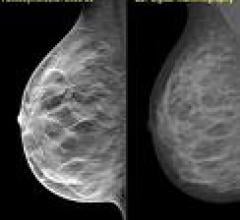

Despite decades of progress in breast imaging, one challenge continues to test even the most skilled radiologists ...